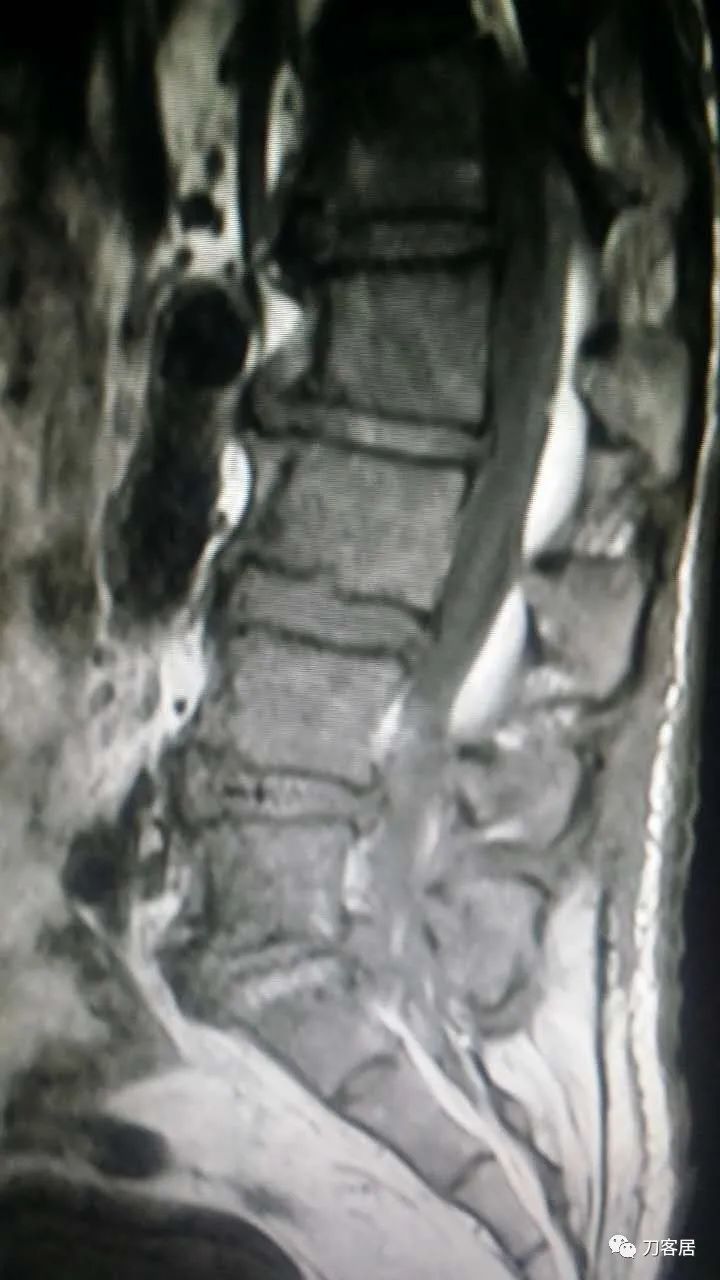

加注图1. 术前腰椎MRI提示腰4-5,腰5骶1椎间盘突出。

加注图12. 术前腰椎MRI,提示腰4-5,腰5骶1椎间盘突出,腰1-2椎管内无占位病变的信号。

加注图13. 术前腰椎MRI,提示腰4-5,腰5骶1椎间盘突出,腰1-2椎管内无占位病变的信号。